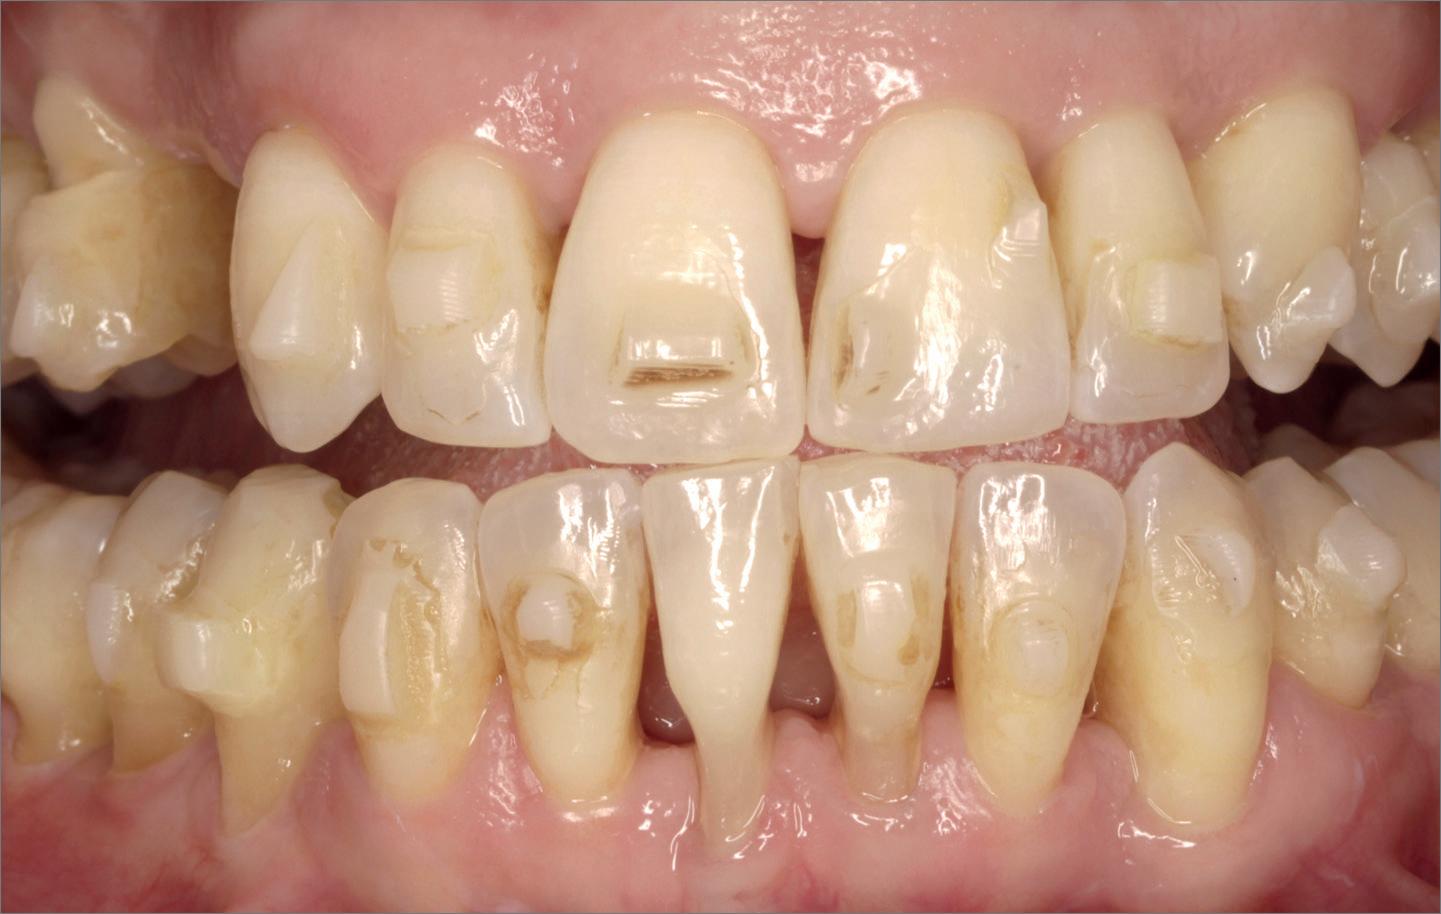

Casus

Een 54-jarige, gezonde man (niet-roker) had in het verleden volledige kroon- en brugwerken in de boven- en onderkaak. Een halfjaar eerder kwam de brug in de bovenkaak los door cariës onder de pijlers. De onderkaak vertoonde eveneens aanhechtingsverlies en pockets dieper dan 6 mm bij enkele elementen. De patiënt gaf direct de voorkeur aan een vaste

brug op implantaten boven een prothese. Vanwege gegeneraliseerde parodontitis in de onderkaak werd het volgende behandelplan opgesteld:

Voor een vaste brug is het belangrijk dat er zo spoedig mogelijk na de (totaal)extracties wordt gestart met het implanteren en de kaakverbredingen, het liefst immediaat. Hoe verder de resorptie gaat, des te meer roze porselein gebruik nodig is. Tegenwoordig wordt er geen porselein meer gebruikt, maar wordt het zirkoonoxide roze ingekleurd. Alleen bij immediaat geplaatste implantaten en direct een tijdelijke brug om de weefsels te ondersteunen, kunnen de witte elementen en de roze mucosa in harmonie zijn zoals in de natuurlijke situatie. Carl Misch (1993) heeft dit in zijn boek beschreven als Fixed Prosthodontics 1 (FP1). Is er verticale resorptie van weefsels, dan moet een compromis worden gekozen tussen onnatuurlijke lange elementen (FP2) of een combinatie van elementen met roze inkleuring van de mucosa (FP3).

Gezien er in deze casus eerst gekozen moest worden

voor een noodprothese, omdat er spoed was en de parodontale ontstekingen in de onderkaak tegelijk behandeld moest worden, werd hier gekozen voor een compromis met FP3 als vaste brug.